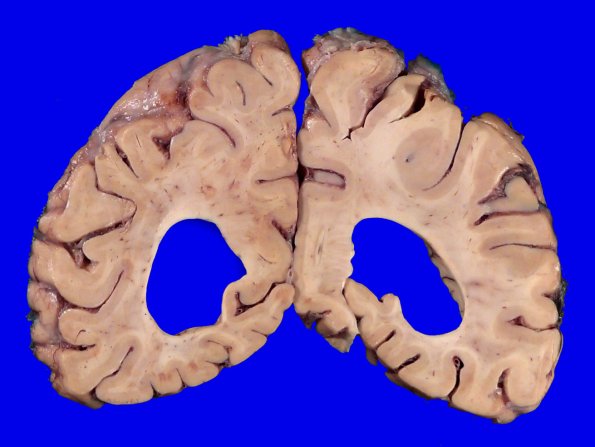

The parieto-occipital lobes participate in the atrophic gross picture.